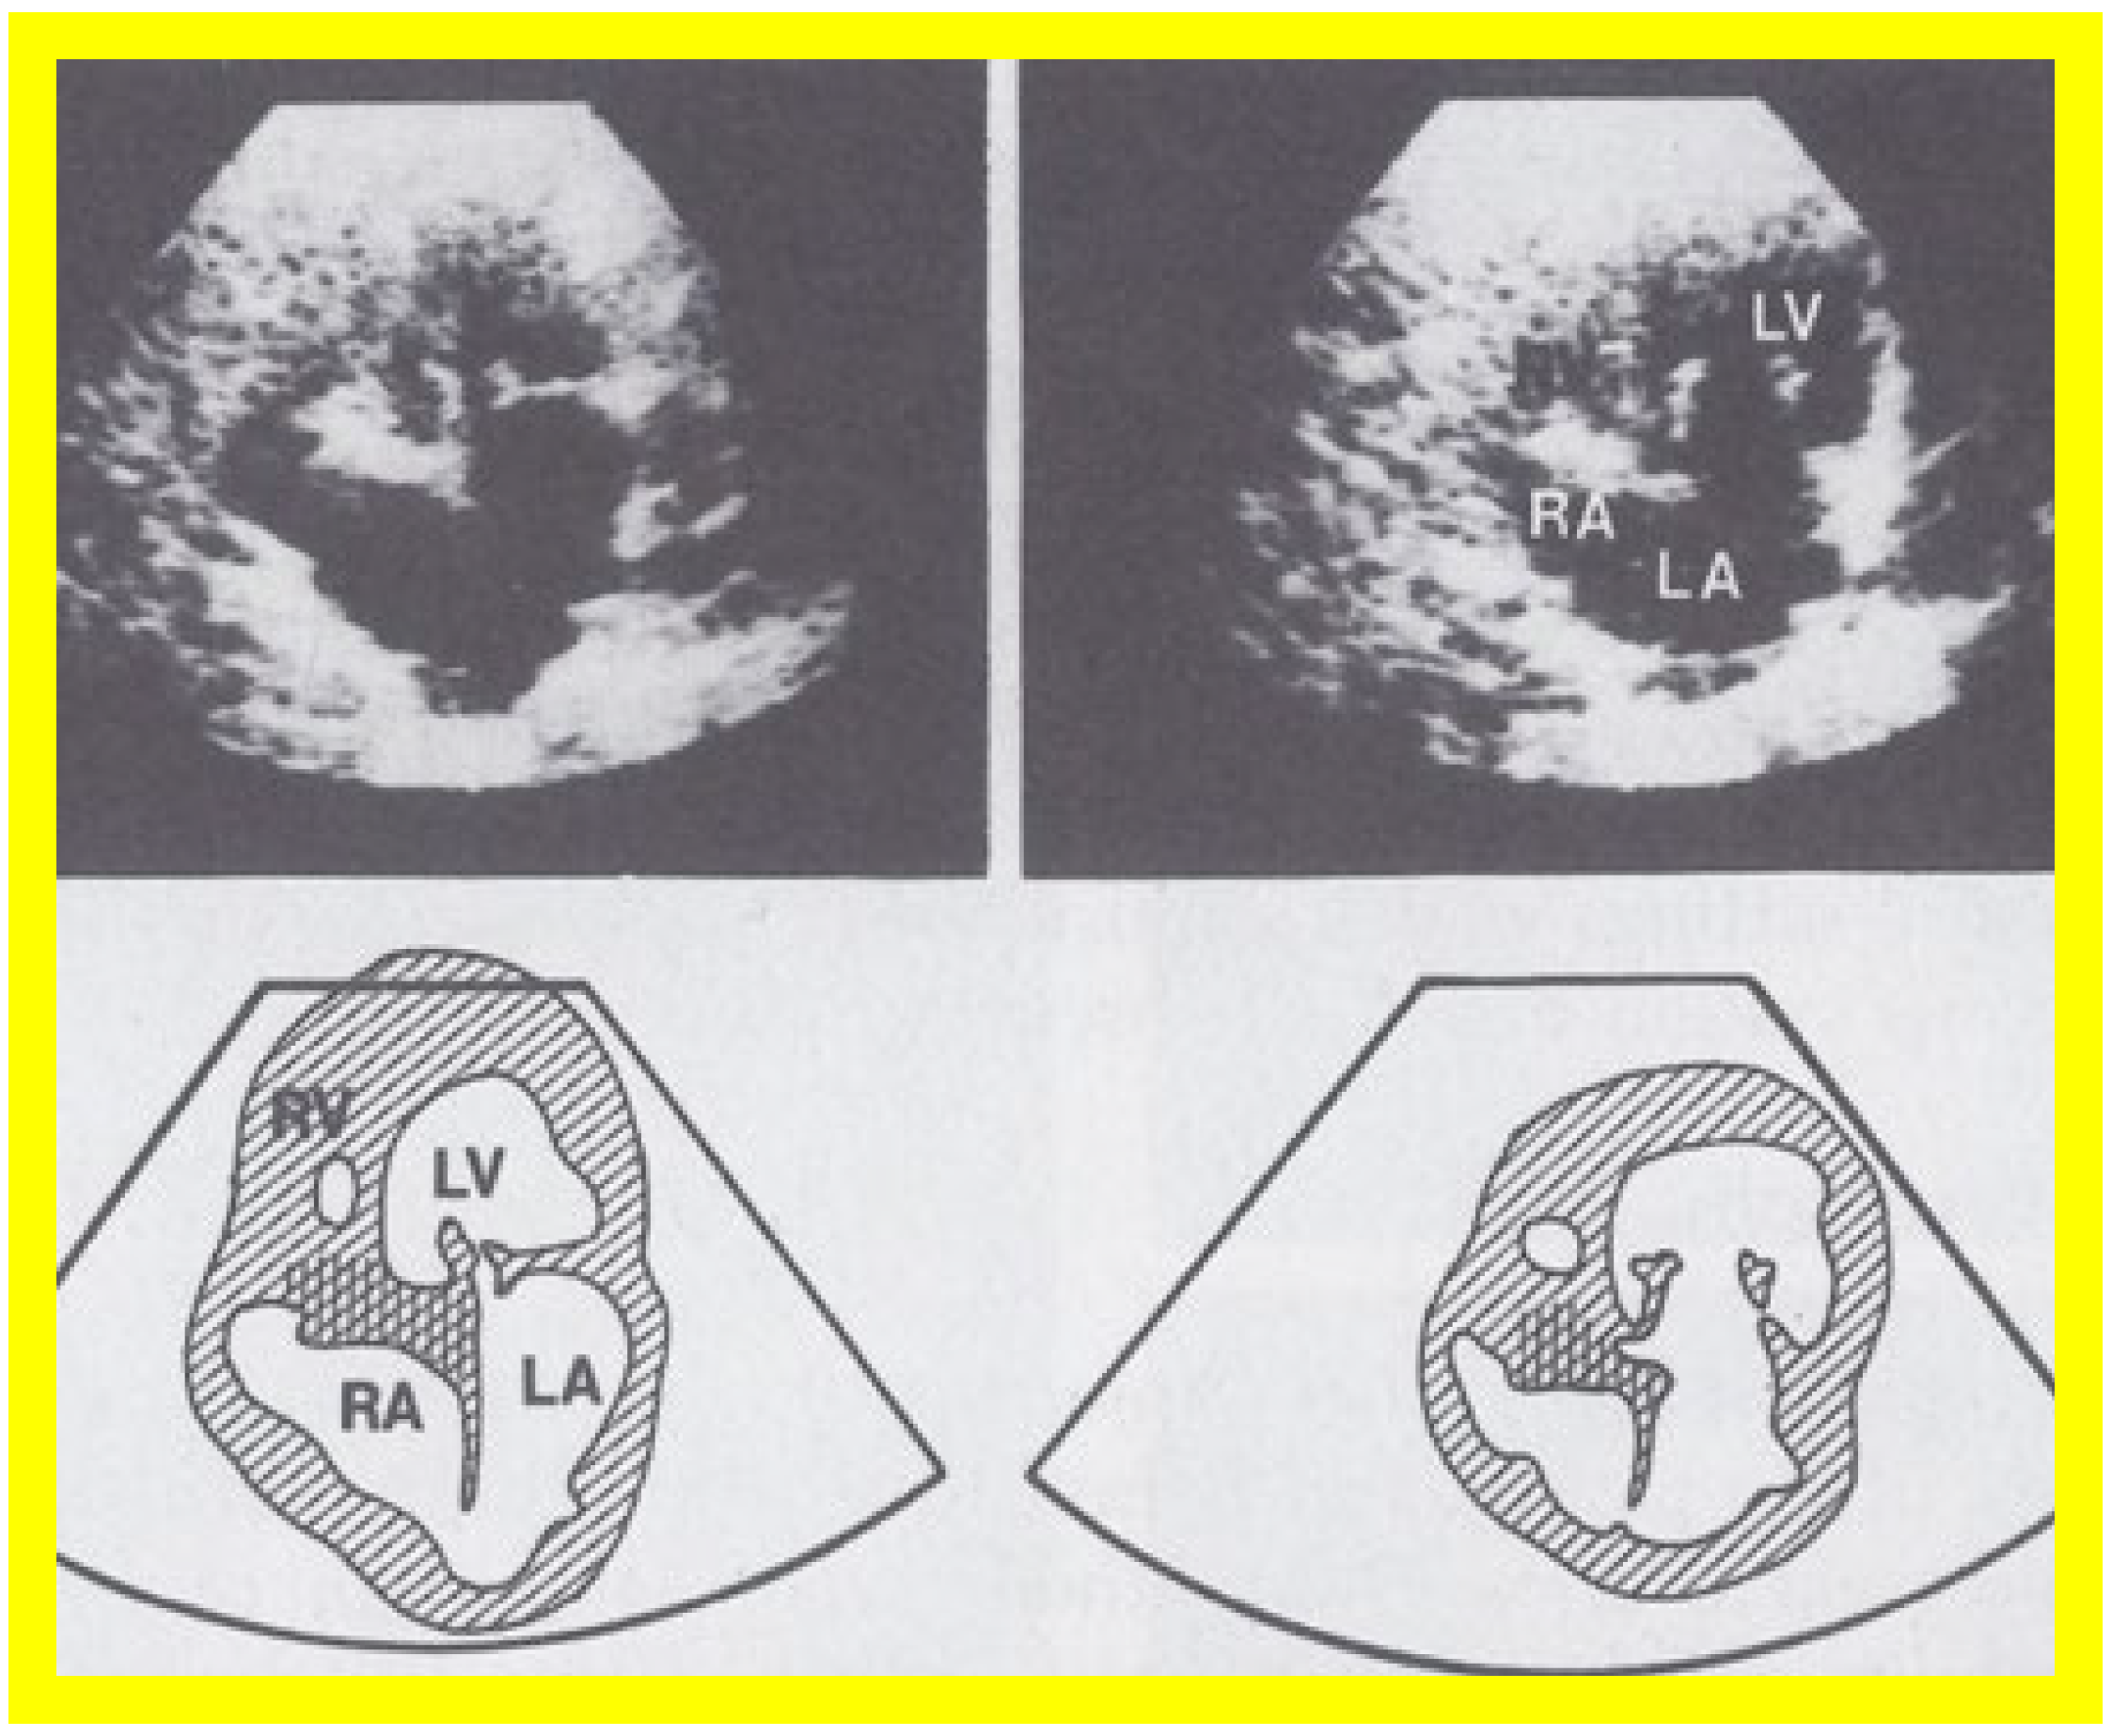

At the time of the preparation of the manuscript for the author’s first edition of the book on tricuspid atresia [23], two dimension (2D) echocardiography was being introduced into clinical practice and the 2D pictures were crude, requiring us to juxtapose line drawings [24] to facilitate interpretation of the figures (Figure 3). The published 2D pictures of TA [25,26], prior to ours, were equally crude. These pictures [24,25,26] represented the state of the art echocardiography machines of that time.

Figure 3. Selected video frames from apical four chamber view of a two dimensional (2D) echocardiographic study, demonstrating a dense band of echoes between the right atrium (RA) and hypoplastic right ventricle (RV). Line drawings are shown beneath the 2D frames. Note that the mitral valve is closed in the left image, while it is open in the right image. The atretic tricuspid valve echoes remain unchanged. LA, left atrium; LV, left ventricle. Reproduced from Reference [24].